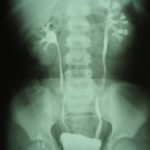

Для підтвердження наявності хвороби проводиться урологічне обстеження, що включає:

- аналіз крові та сечі;

- сканування нирок;

- урографію;

- радинуклеидную ренографию та інше.

Найчастіше в процесі обстеження застосовується радіонуклідна ренографія. Так, зменшення судинного сегменту ренограммы вказує на наявність поразок. Такий спосіб особливо дієвий при односторонньому ураженні артерії нирок, у цьому випадку відзначається двостороння асиметричність ренограмм.

Як правило, рентген проводиться після ренографії, коли визначена уражена сторона. А при проведенні урографії часто виявляється «німа» нирка або раптове пригнічення її функціонування.

Важливе значення у діагностиці вазоренальної АГ має динамічна сцинтиграфія. З її допомогою можна виявити рівень стенозу ниркової артерії та оцінити зміни в паренхімі нирки.

Остаточний діагноз ставлять, використовуючи ангіографію, що дозволяє визначити звуження або інші зміни в просвіті ниркової артерії. Також такий діагностичний метод визначає метод лікування захворювання.